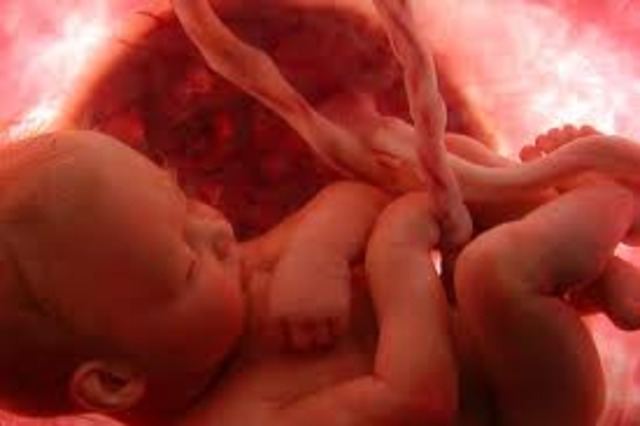

• month 9 the last month

month 9 the last month

this is the last month for the baby and mommy both are ready for delivery the baby is alredy in position still is gaing weight skin becomes soft moving around is less active because of the room left the baby gets disease fighting antibodys from mothers blood the baby goes althe way to pelvis ready to be born